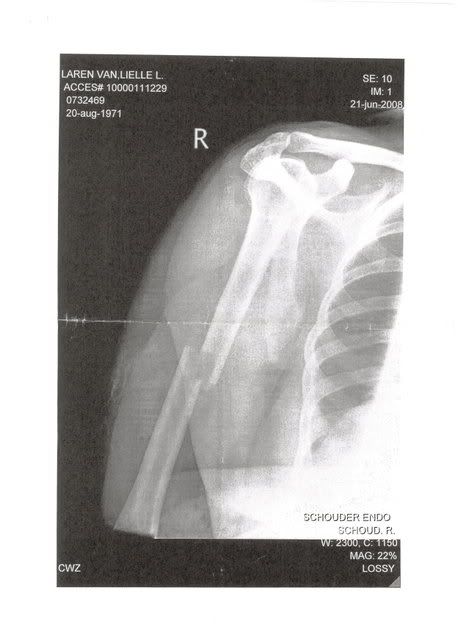

Na 3 uur op de eerste hulp te hebben gezeten mochten we eindelijk zo'n kamertje in, de dokter ging voelen en zei dat hij dacht aan een spierenkwestie maar helaas, na het zien van de foto kwam hij nogal gehaast terug en zei dat hij slecht nieuws had.

Mijn schouder is gebroken, net onder de schouderkop, volgens hem werd dit een vreselijk zwaar en pijnlijk proces.